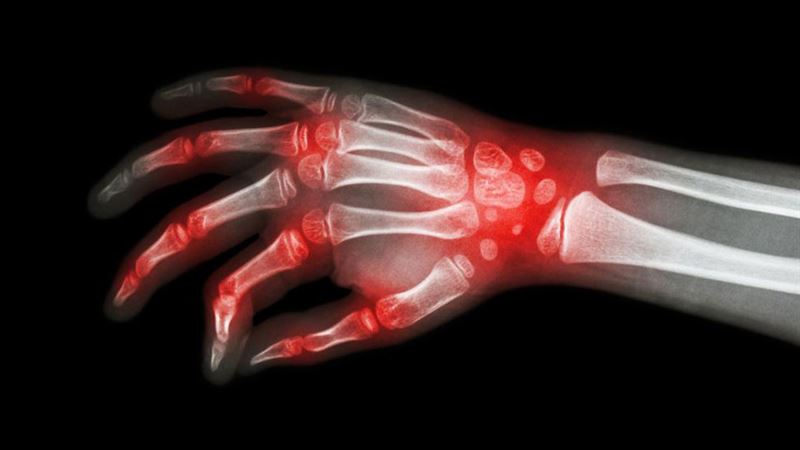

Rheumatoid arthritis (RA) is a chronic autoimmune disorder that predominantly targets joints, leading to inflammation, pain, swelling, and eventual joint destruction if left untreated. Combating this condition requires a multifaceted approach that combines medication, lifestyle changes, physical therapy, and sometimes surgical intervention to manage symptoms effectively and improve patients' overall well-being.

Understanding the complexity of RA is essential. It is characterized by the immune system mistakenly attacking the synovial membrane lining the joints, which results in persistent inflammation. Over time, this inflammation can erode cartilage, bone, and surrounding tissues, leading to deformities, loss of function, and in severe cases, disability. Early diagnosis and prompt treatment are crucial to slow progression and preserve joint integrity.